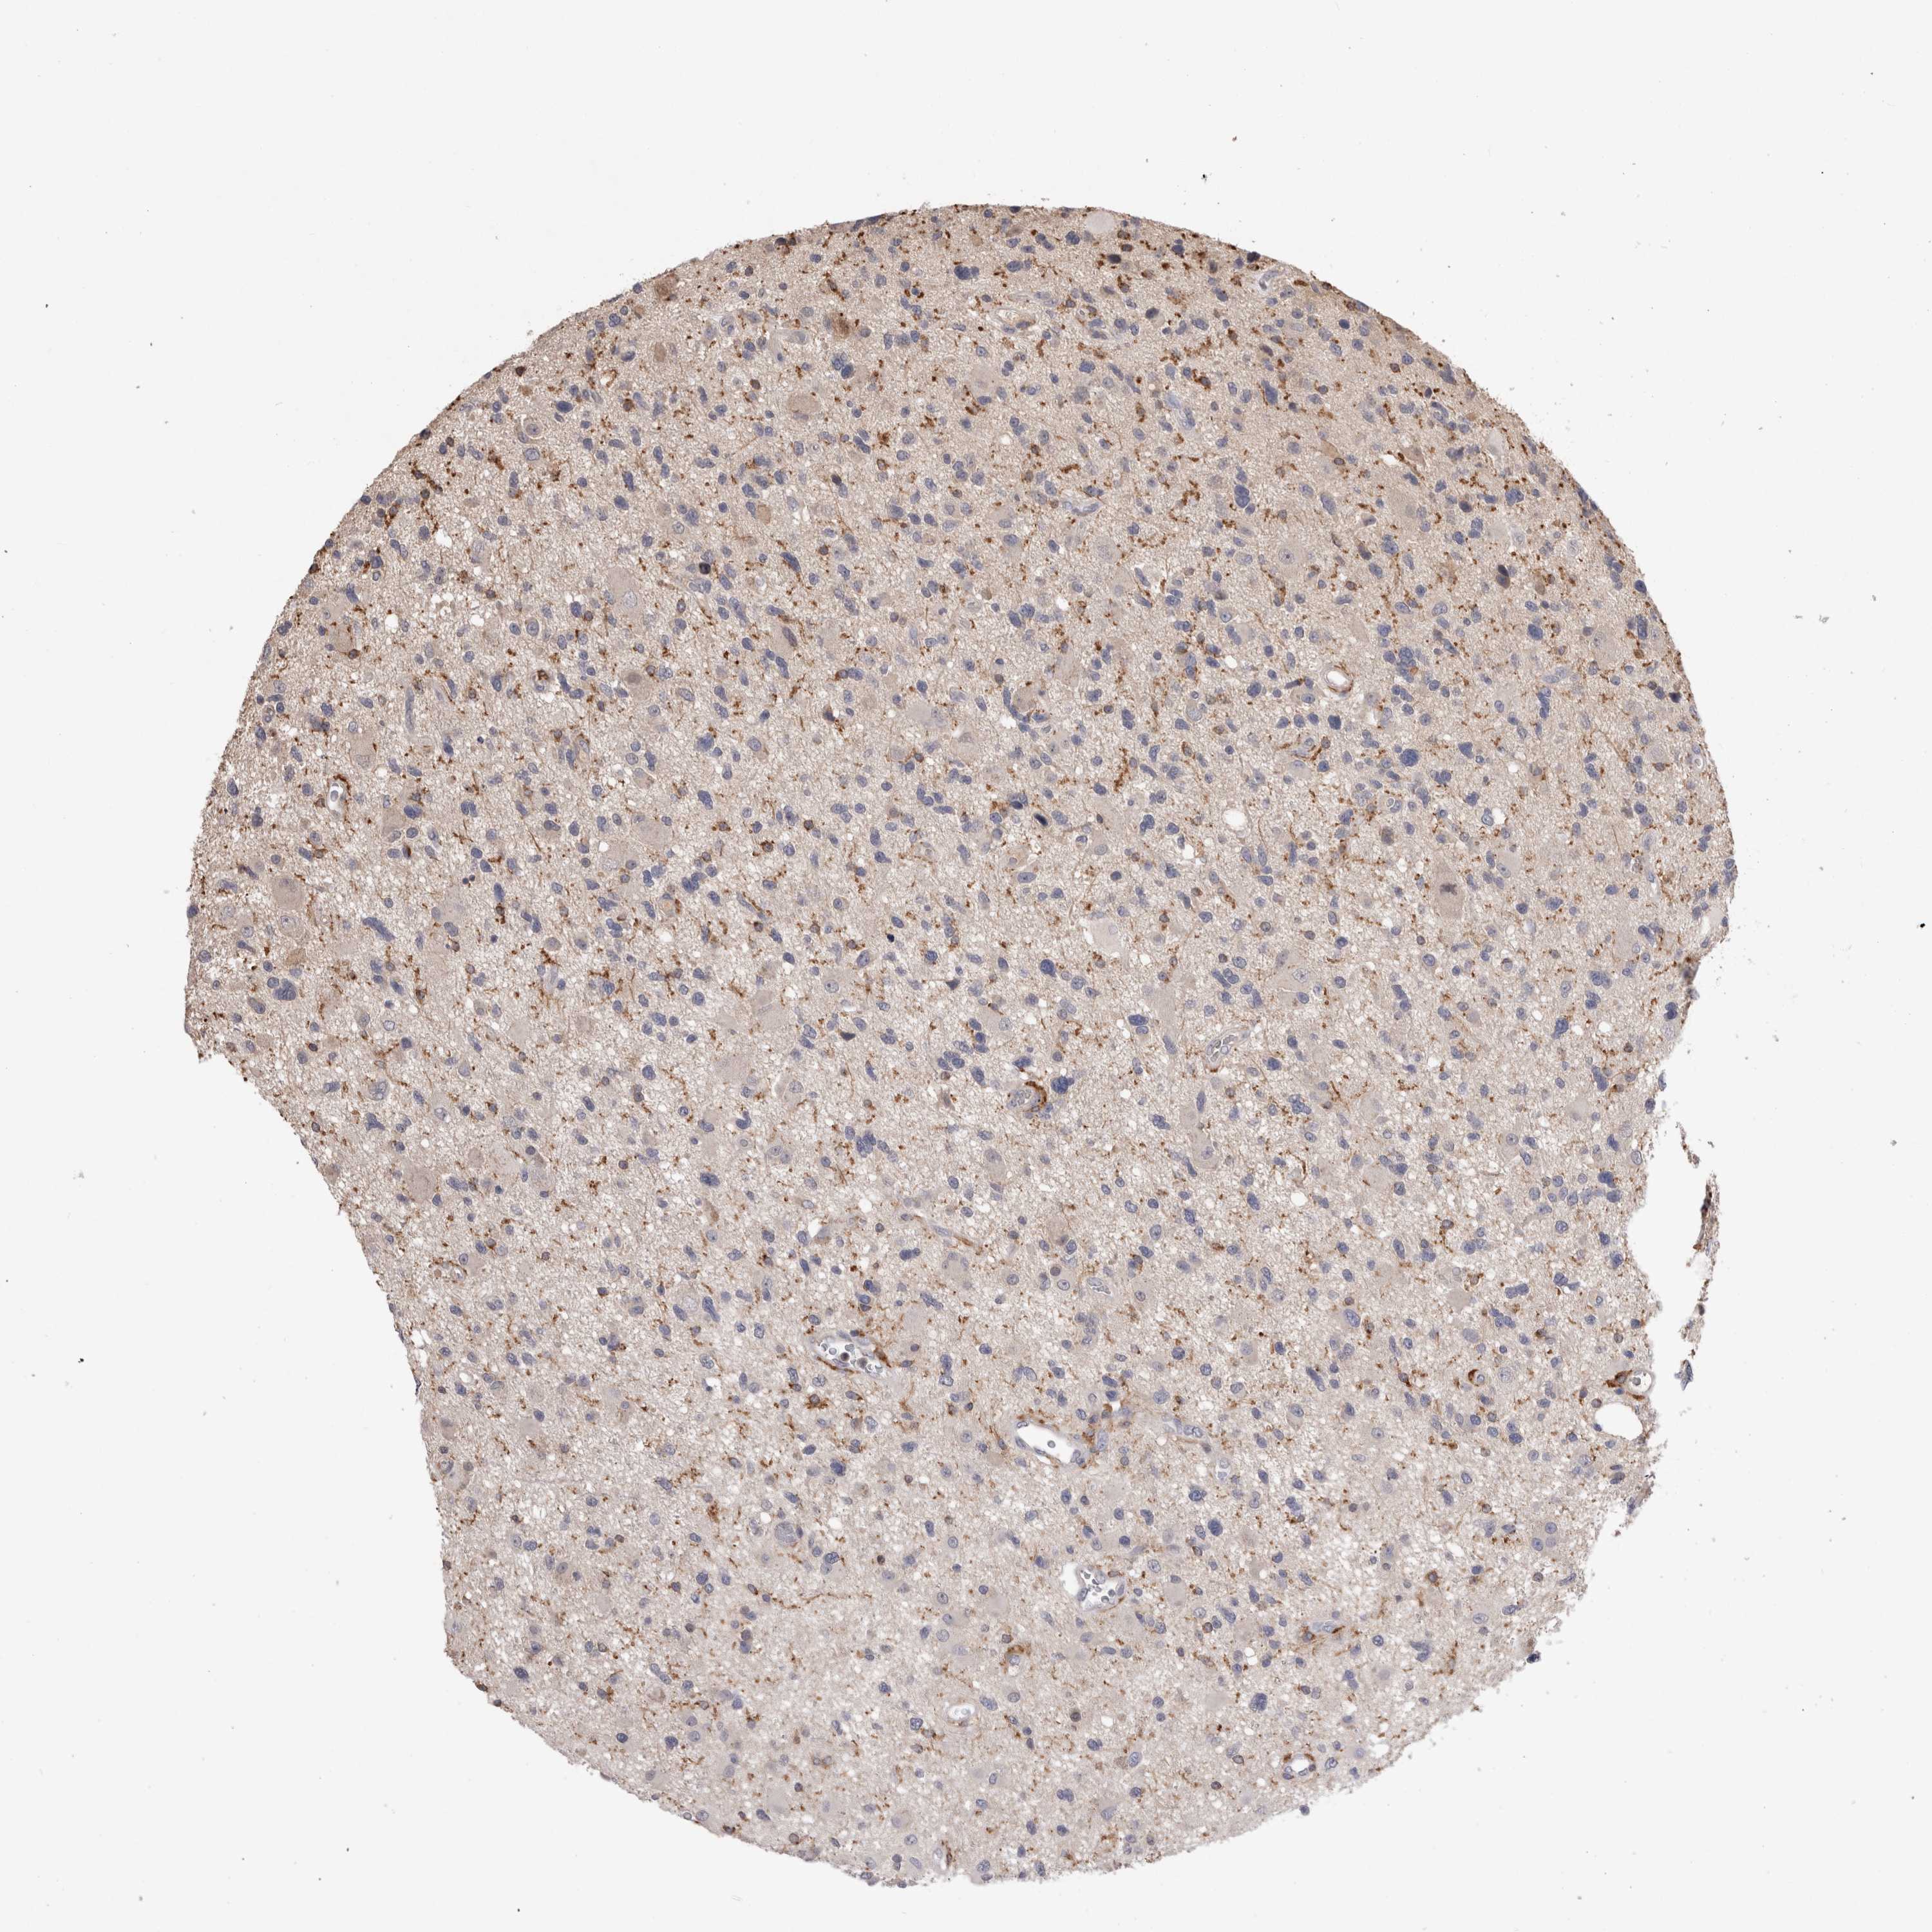

GLIOMA - Protein expressioni

A mouse-over function shows sample information and annotation data. Click on an image to view it in a full screen mode. Samples can be filtered based on level of antibody staining by selecting one or several of the following categories: high, medium, low and not detected. The assay and annotation is described here.

Note that samples used for immunohistochemistry by the Human Protein Atlas do not correspond to samples in the TCGA dataset.

Antibody stainingi

Antibody staining in the annotated cell types in the current human tissue is reported as not detected, low, medium, or high, based on conventional immunohistochemistry profiling in selected tissues. This score is based on the combination of the staining intensity and fraction of stained cells.

Each image is clickable and will lead to virtual microscopy that enables deeper exploration of all samples and also displays staining intensity scores, fraction scores and subcellular localization as well as patient and tissue information for each sample.

Antibody HPA003903

Antibody HPA072756

Antibody CAB026000

Staining

High

Medium

Low

Not detected

Intensity

Strong

Moderate

Weak

Negative

Quantity

>75%

75%-25%

<25%

None

Location

Nuclear

Cytoplasmic/membranous

Cytoplasmic/membranous,nuclear

Glioma, malignant, High grade

Glioma, malignant, NOS

Glioma, malignant, Low grade